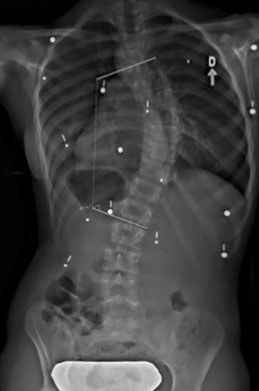

Étude de cas d’une autre adolescente avec une scoliose

Le cas d'une adolescente âgée de 12 ans et 9 mois (Risser 0) au début du traitement.

Cette jeune fille, dont la photographie montre une difformité importante du dos, souffre d’une scoliose déjà sévère dont la courbe atteint 42° (angle de Cobb) au début du traitement.

Dès l'installation du SpineCor®, on note une réduction de la courbure grâce à l'action dynamique des bandes élastiques malgré une scoliose très importante.

Après 30 mois de traitement, la scoliose est stabilisée à 33° et la croissance terminée. Il est normal avec une courbure d'amplitude aussi marquée de remarquer une légère perte de correction par rapport au premier jour du traitement, car la colonne vertébrale de la patiente a continué de grandir durant le traitement et la courbe d'évoluer. Quand on débute plus jeune le traitement sur des scolioses de moindre amplitude, il est souvent possible d'éviter ces phases d'aggravation.

Mais au final, la dernière photographie prise après le sevrage du traitement montre clairement que la posture de la jeune fille présente un aspect beaucoup plus normal et symétrique qu'au début. Grâce à SpineCor®, l'esthétique de son dos s'en trouve améliorée encore plus que la correction réelle de sa courbe, ce qui aura inévitablement un effet positif direct sur son image de soi.